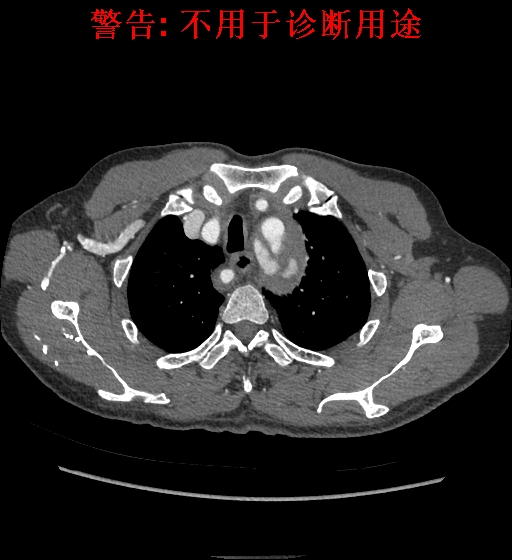

典型征象

CT 平扫见气管右侧类圆形结节影,易误诊,但连续层面观察见类圆形结节行走于食管后方,少数行走于食管气管间或气管前,往右上方走行向腋窝方向延伸;

CT 血管造影见迷走右锁骨下动脉起始于主动脉弓或降主动脉;

MIP 冠状位显示主动脉弓下缘“象鼻样”发出的血管,常由左下向右越过中线向上延伸,轴位则常为“鸟嘴样”改变。

诊断:B型主动脉夹层、主动脉壁间血肿、迷走右锁骨下动脉。

诊断:B型主动脉夹层、高血压、迷走右锁骨下动脉。

诊断:主动脉夹层,壁间血肿。